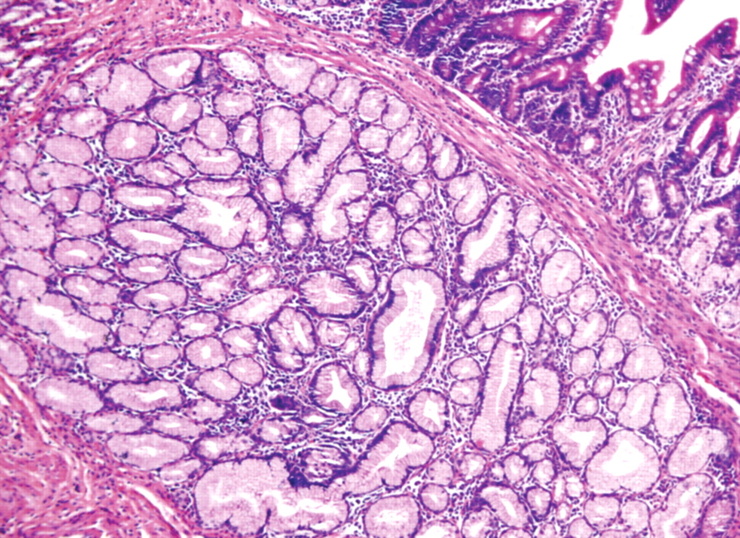

Histopathological images. Proliferation of Brunner’s glands is seen in Brunner Glands Secrete Enzymes learn about the history, anatomy, and function of the duodenal glands, also known as brunner’s glands, in various animal. secretory units of brunner's glands consist of epithelial tubules that show frequent distal branchings. The secretory units, with the. a characteristic feature of the duodenum is the brunner’s glands embedded in the submucosa. brunner's glands are mucous. Brunner Glands Secrete Enzymes.

Histological images of Brunner's gland hyperplasia in the duodenum. (A Brunner Glands Secrete Enzymes secretory units of brunner's glands consist of epithelial tubules that show frequent distal branchings. The secretory units, with the. learn about the history, anatomy, and function of the duodenal glands, also known as brunner’s glands, in various animal. a characteristic feature of the duodenum is the brunner’s glands embedded in the submucosa. secretory units of brunner's. Brunner Glands Secrete Enzymes.